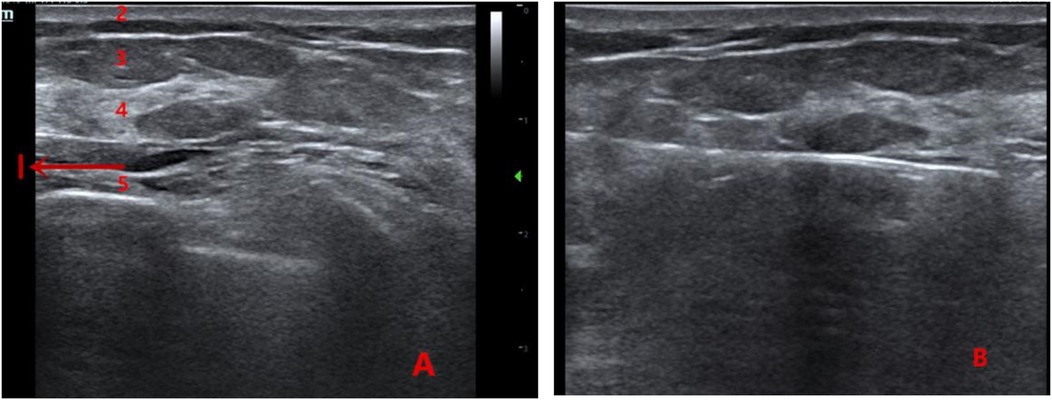

A 4–5 mm incision was made at the puncture site. Under ultrasound guidance, the rotary excision needle was inserted through the shortest distance of glandular tissue into the expanded retromammary space beneath the nodule. The needle was adjusted so that the cutting groove was positioned beneath the nodule. The lesion was excised using a fan-shaped rotational movement, with continuous adjustment of the needle under real-time ultrasound guidance. Vacuum aspiration was used to remove residual blood. After confirming the absence of residual tissue using a crosswise inspection technique, the needle was withdrawn, residual blood was expressed from the cavity, and the incision was covered with a sterile dressing. Firm compression was applied over the incision and cavity for 5 min, and an elastic bandage was applied for at least 48 h. The rotary excision needle was flushed with 250 mL of normal saline, and the specimen was collected (Figure 1).

Figure 1. (A) Ultrasound image showing the anatomical layers of the breast (1: anechoic area formed by local anesthetic swelling in the retromammary space; 2: skin layer; 3: fat layer; 4: glandular layer; 5: pectoralis muscle layer). (B) Intraoperative view of the retromammary-space VAE procedure.